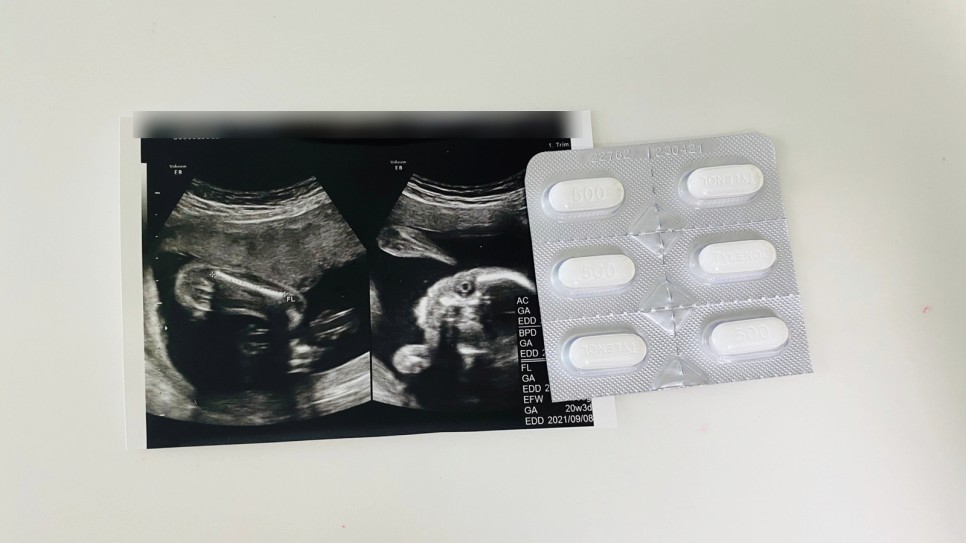

• 두통과 감기약 괜찮을까? 임부 타이레놀

괜히 뭐 먹기 힘든 임산부 두통과 감기약 타이레놀 괜찮을까?건

강한 임신생활을 위해 이것저것 알아보는 마더에요. 태아를 위해 임산부라면 참아야할게 정말 많아요. 어려운 것 중 하나가 임신 중 여러 가지 증상에 대해 뭔가 먹어도 괜찮은가? 이 많아요일반적인 음식에서 시작해서 약물이 특히 그래요.특히 임신 초기부터 잦은 임산부 두통이나 방심하면 걸리는 임산부 감기, 그럴 때 권장하는 약과 먹으면 안 되는 것이 무엇이 있는지, 일반적으로 괜찮다고 이야기하는 것이 무엇이 있는지 알아봅시다.

일단 임산부 타이레놀 책 정말 괜찮을까?

아이들의 해열 진통제로도 사용되는 아세트아미노펜 계열로 구성된 것이 이 놀이입니다. 이 밖에 비슷한 효과를 생각하신다면, 부루펜이나 아스피린 계열도 신경이 쓰이는데요.

임신 중 감기 등의 원인으로 고열이 나면 참는 것이 오히려 위험하므로 치료와 함께 적당한 약을 추천합니다. 특히 초기의 경우 자연유산이나 태아기형 등 우려되는 점이 많기 때문에 임신부라 하더라도 진료와 약물처방을 피할 것이 아니라 일단 상담 후 적절하게 써야 한다는 점!이 반드시 필요합니다. 이 때 해열제로 사용하는 것이 아세트아미노펜 계열의 타이레 놀이입니다.

임산부 타이레놀 임신두통과 감기약 괜찮을까?

고민하고 있을 때, 이럴 때 머터니티 타이레놀은 임신 두통뿐 아니라 임산부 감기에 의한 발열 때에도 사용할 수 있어요. 쉽게 쓸 수 있겠죠? 그러나 안전하다고 해서 장기 복용은 금물이라는 것을 기억해 두시기 바랍니다.

일반적인 아세트아미노펜이 들어 있는 종류가 아니면 함부로 먹지 말고(부루펜이나 아스피린 등) 경옥 성분 등을 확인하십시오. 불안하다면 산부인과 검진일이나 가까운 내과에 임신 중임을 밝히고 처방을 받은 후 사용하는 것이 가장 좋습니다.